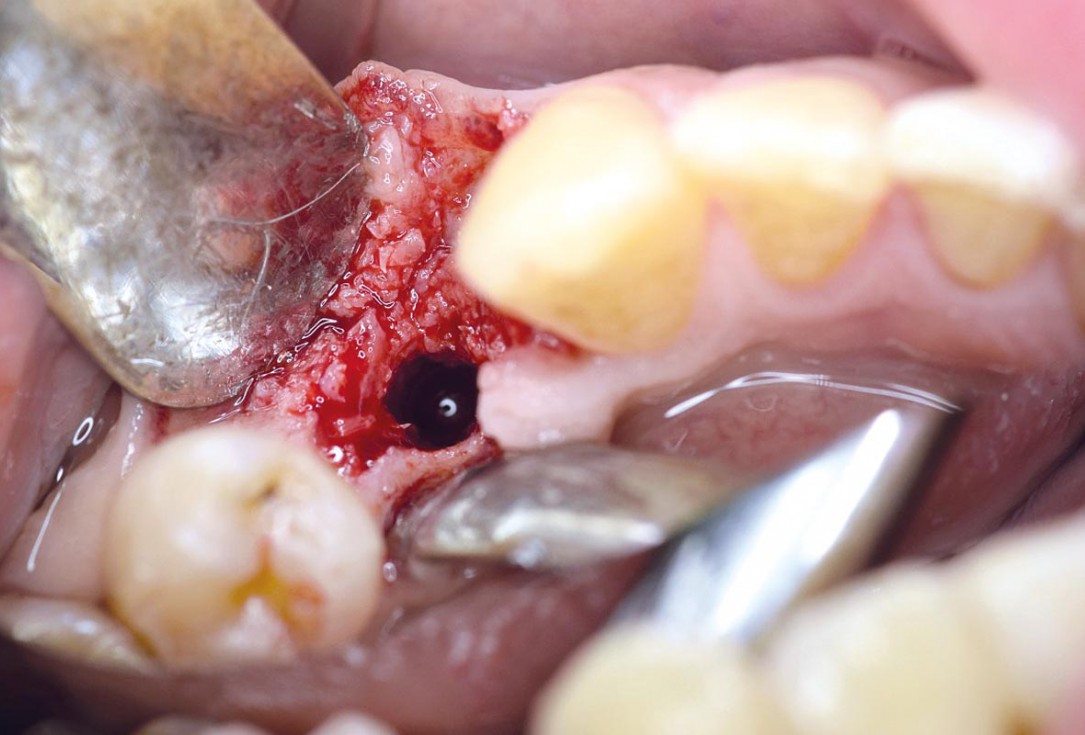

Preparation of a single tooth defect with severely resorbed vestibular wall

Posterior socket preservation using maxgraft® and permamem® - Dr. C. Landsberg